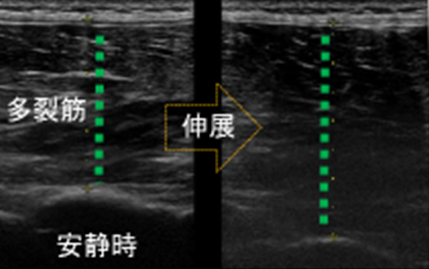

超音波検査装置を用いて

![]() |

筋厚変化率:収縮時筋厚/安静時筋厚

|

骨密度や筋力、運動機能などから、適切な対処法を導きます。